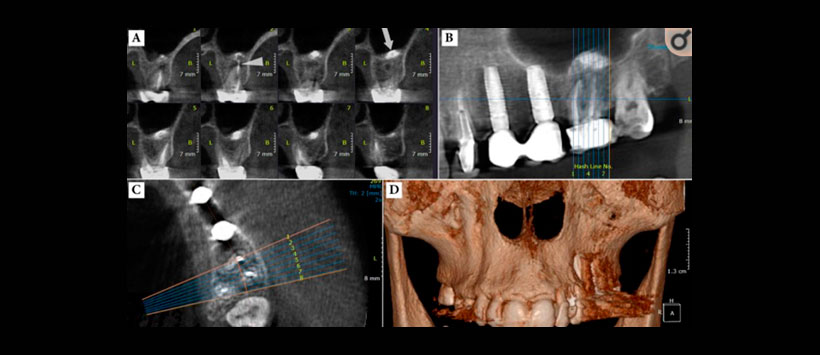

- Periodontitis apical – Figura 1